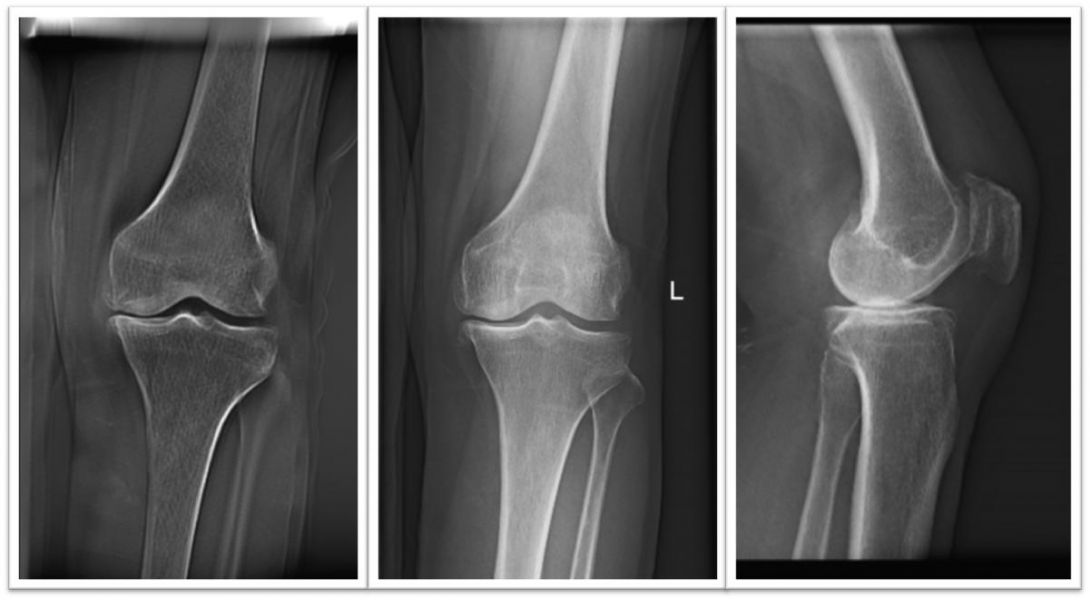

彭某,53岁,因左膝骨关节炎入院,入院前该患者长期饱受左膝病痛折磨,症状反复,辗转各地到处求医问药,病情却一直不见好转。保守治疗无效,外院的医生认为她只有进行人工全膝关节置换手术才能彻底根治,但患者害怕手术疼痛,且认为自身还年轻,更加担心关节松动、假体下沉等风险。为得到专业权威的诊疗方案,彭某慕名找到州医院骨一科赵峻主任医师。赵峻主任针对她的病情进行了分析讨论后,为彭某制定了单髁置换保膝手术方案,这样不仅能通过微创手术为她彻底解决内侧关节间隙退变磨损的痛苦,还能为她保留膝关节的解剖结构、本体感觉及骨量,具有微创、恢复快、出血少、花费少等优点。完善相关术前准备后,赵峻主任医师带领团队仅耗时不到60分钟便成功为彭某完成了单髁置换手术。术后第二天早晨,彭某就可下地行走、活动良好,术前疼痛感消失,仅有伤口轻微疼痛。彭某感慨:“来州医院之前以为必须通过全膝关节置换大手术来解决膝关节顽疾,没想到微创小手术能解决大烦恼,现在手术后行走自如,术前疼痛感完全缓解”。

术前膝关节正侧位片